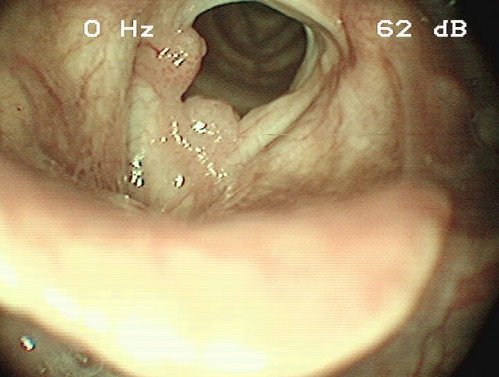

Nichtraucher mit Heiserkeit seit mehreren Jahren

Ein 52-jähriger Patient berichtet über eine Heiserkeit, die seit mehreren Jahren bestünde und sich in den letzten Monaten deutlich verstärkt habe. Er ist Nichtraucher und hat ansonsten keinerlei gesundheitliche Beschwerden.